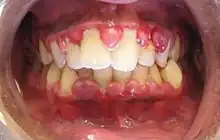

| A severe case of gingivitis | |

Gingivitis is a non-destructive disease that causes inflammation of the gums;[1] ulitis is an alternative term.[2] The most common form of gingivitis, and the most common form of periodontal disease overall, is in response to bacterial biofilms (also called plaque) that are attached to tooth surfaces, termed plaque-induced gingivitis. Most forms of gingivitis are plaque-induced.[3]

The symptoms of gingivitis are somewhat non-specific and manifest in the gum tissue as the classic signs of inflammation:

- Swollen gums

- Bright red gums

- Gums that are tender or painful to the touch

- Bleeding gums or bleeding after brushing and/or flossing

- Bad breath (halitosis)

Additionally, the stippling that normally exists in the gum tissue of some individuals will often disappear and the gums may appear shiny when the gum tissue becomes swollen and stretched over the inflamed underlying connective tissue. The accumulation may also emit an unpleasant odor. When the gingiva are swollen, the epithelial lining of the gingival crevice becomes ulcerated and the gums will bleed more easily with even gentle brushing, and especially when flossing.